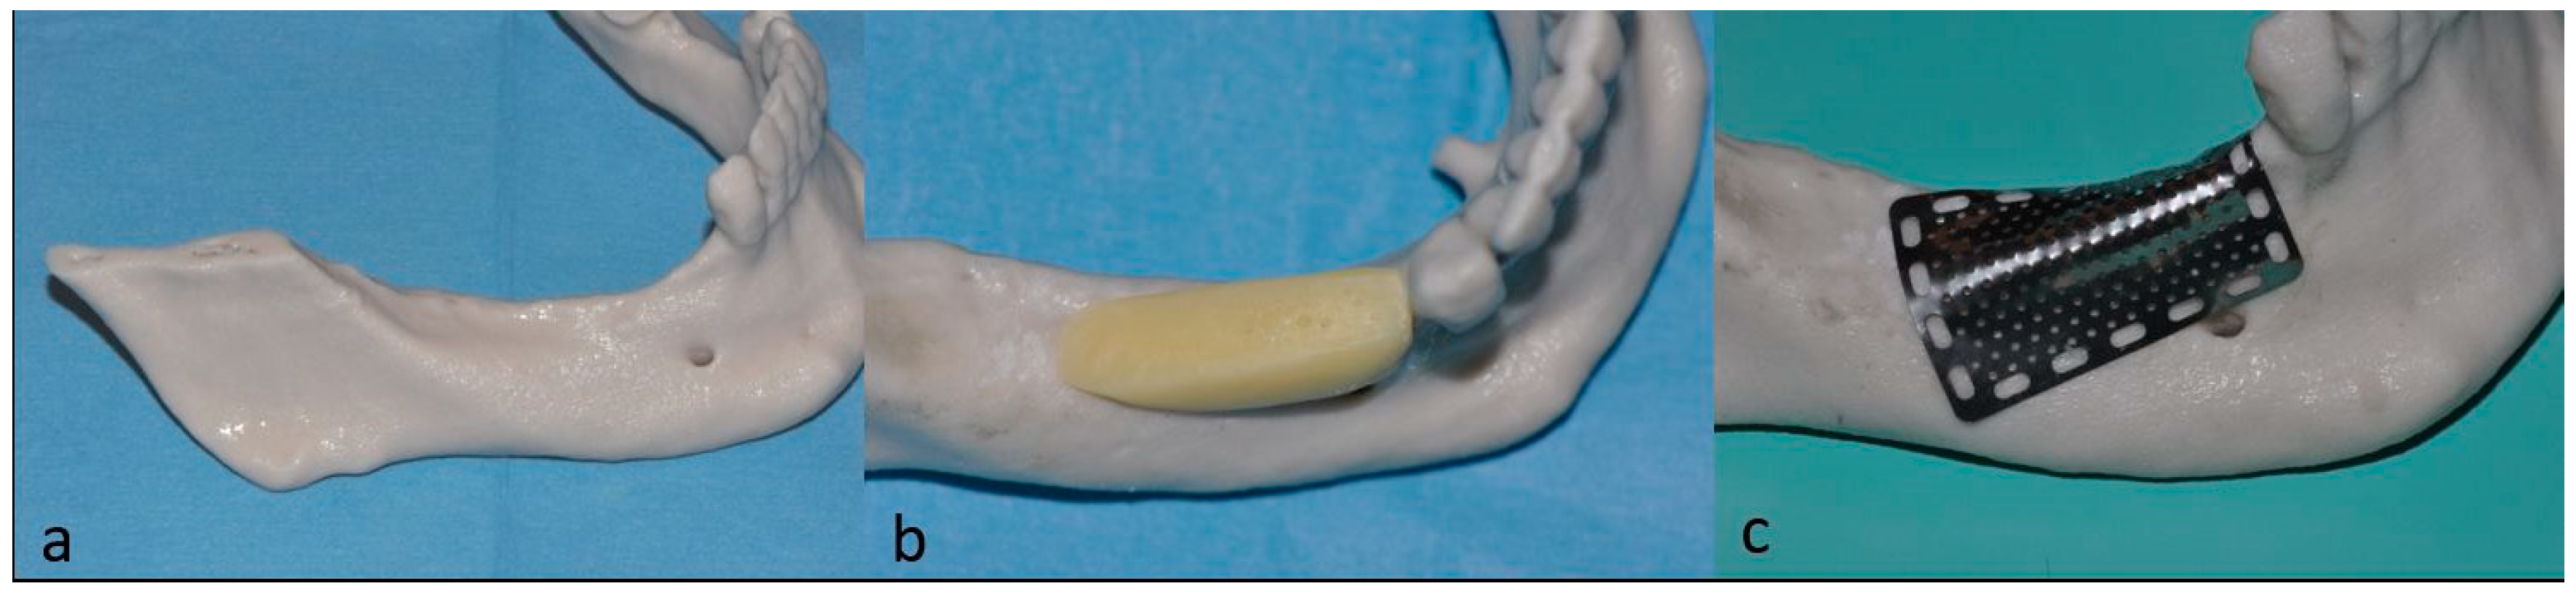

- Di Stefano, D.A.; Greco, G.B.; Cinci, L.; Pieri, L. Horizontal-guided Bone Regeneration using a Titanium Mesh and an Equine Bone Graft. J. Contemp. Dent. Pract. 2015, 16, 154–162. [Google Scholar] [CrossRef] [PubMed]